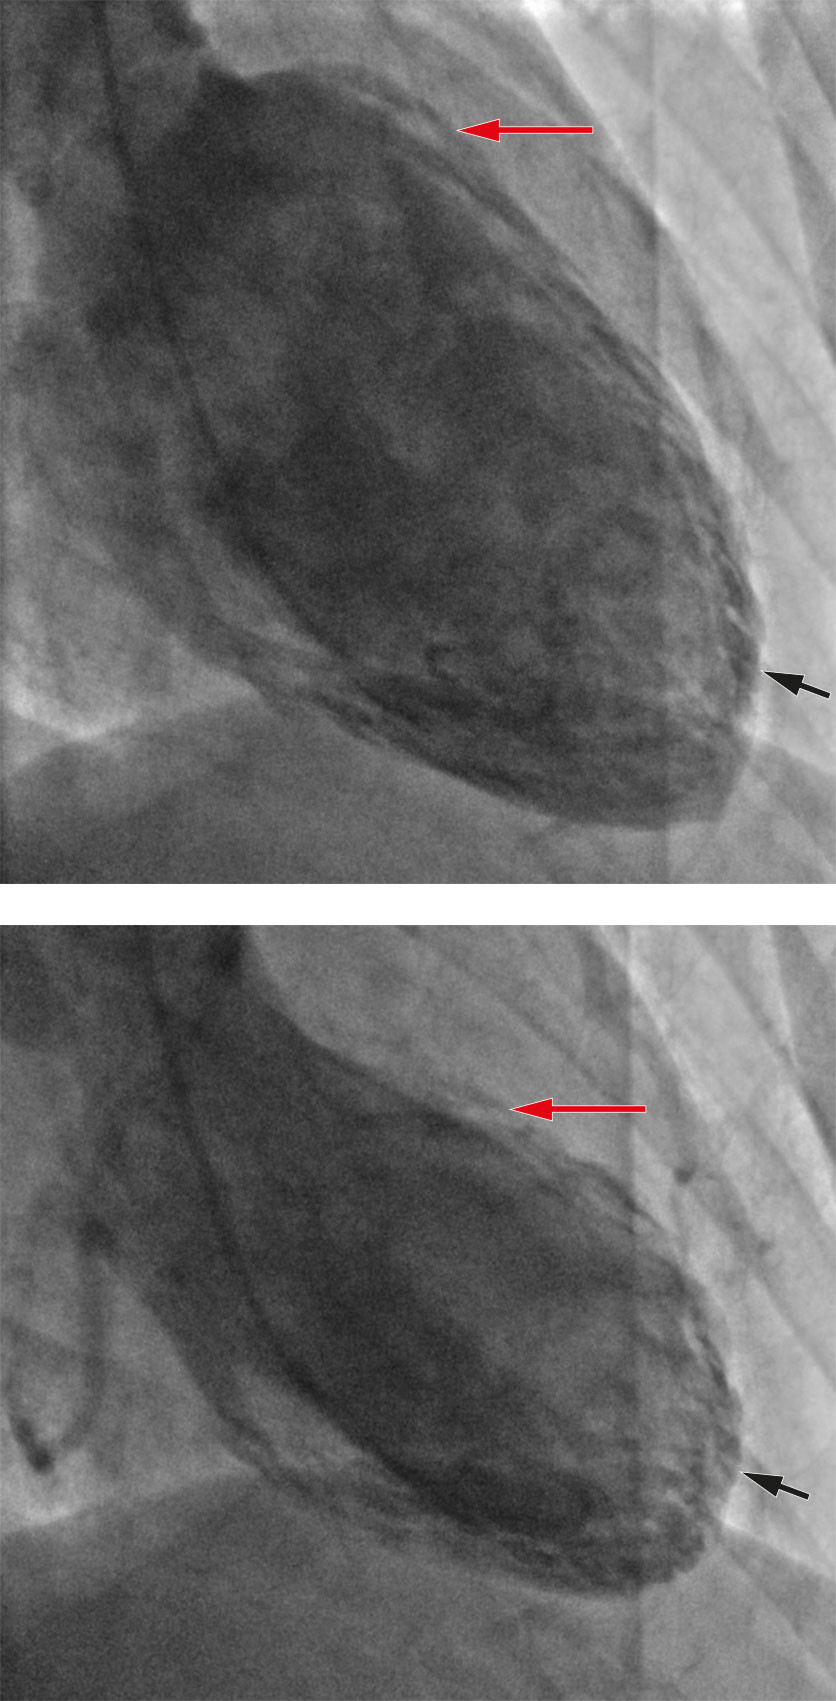

Coronary angiography revealed normal coronary arteries, and ventriculography showed apical hypokinesia and basal hypercontractility, typical for Takotsubo syndrome (Figure 2). Treatment with 1.25 mg ramipril was initiated that same evening.